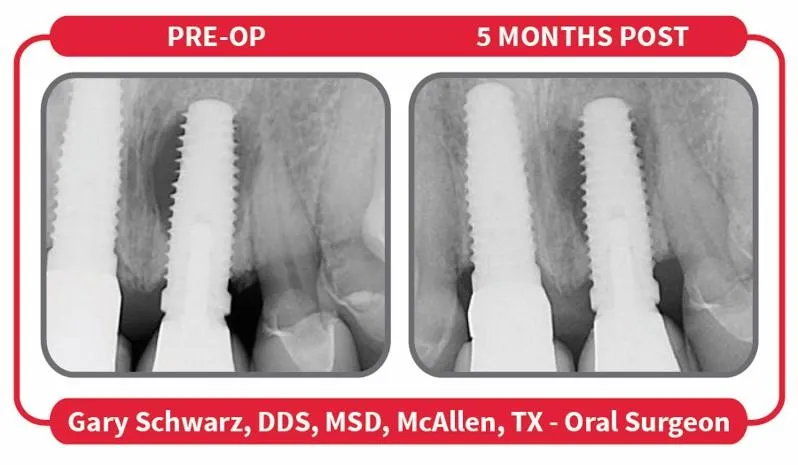

94% of implants with peri-implantitis saved with the LAPIP protocol

11% required 2 treatments

7% required 3 treatments

6% of implants were removed